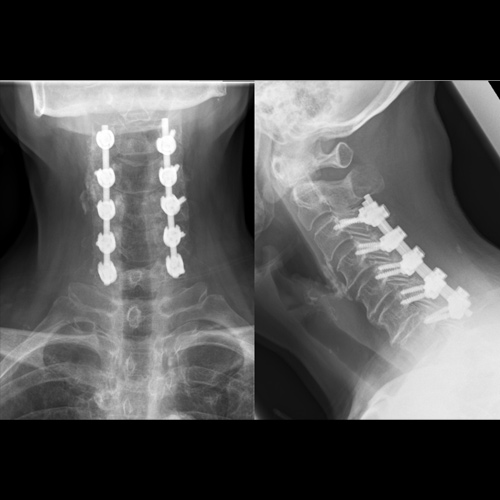

Spinal stenosis (Lumbar) Spinal stenosis (Cervical) Spinal stenosis (Thoracic) Lumbar Disc Herniation Spondylolisthesis Cervical Foraminal Stenosis Vertebroplasty Lumbar Fusion Anterior Cervical Fusion (ACDF) Posterior Cervical Fusion Thoracic Fusion Revision Lumbar Fusion Surgery Facet Joint Cyst Spinal Tumour Minimally Invasive Lumbar Fusion (XLIF) Minimally Invasive Lumbar Fusion (ALIF) Lumbar Fusion (TLIF) Thoraco-lumbar Fusion Lumbar Corpectomy Complex Lumbar Spine Surgery (Spino-pelvic fixation) Complex Cervical Spine Surgery Complex Thoracic Spine Surgery Occipito-cervical Fusion Minimally invasive surgery for thoracic disc herniation Other Related Topics